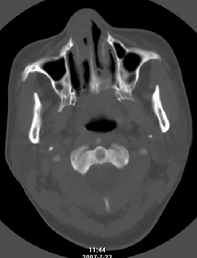

以下是引用还珠格格在2007-7-31 19:32:00的发言:[br]右侧鼻前庭内可见软组织块影,部分鼻中隔包绕其内,邻近骨质未见明显吸收破坏,考虑 1、鼻息肉可能性大 内翻乳头状廇不除外。期待结果。

以下是引用zjzjr在2007-7-31 20:29:00的发言:[br]右侧鼻前庭内可见软组织块影,部分鼻中隔包绕其内,邻近骨质未见明显吸收破坏,考虑 1、鼻息肉可能性大 内翻乳头状廇及肉芽肿类病变除外。期待结果。